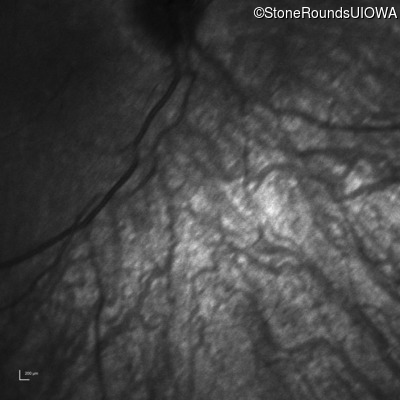

Infrared Fundus Photograph - Left -

No Light Perception

Exemplar

Expanded OCT Stack

×